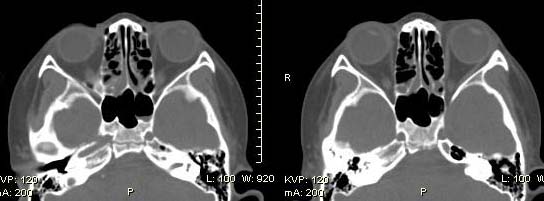

以下是引用随光逐影在2009-6-4 21:13:00的发言:[br]1)考虑鼻咽腺样体重度肥大。2)双侧鼻腔炎性改变。3)双侧上颌窦、双侧筛窦及左侧蝶窦炎症。

以下是引用zsl6918在2009-6-5 7:42:00的发言:[br]首先考虑鼻咽腺样体重度肥大,鉴别纤维血管瘤.强化有助明确.